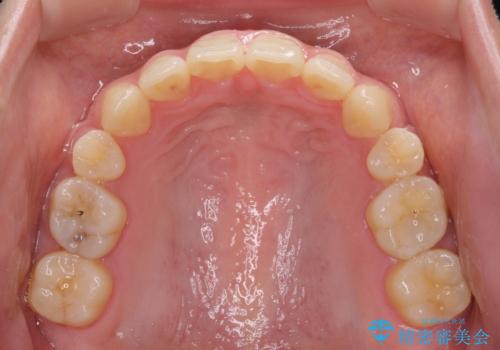

話しにくいオープンバイト ワイヤー装置による抜歯矯正治療

オープンバイトの原因は舌の突出癖であり、癖が改善されないと治療経過に影響を及ぼすため、舌のトレーニングを指示しました。

なかなか癖が改善されず、トレーニングも断続的に行ったため、治療期間は長期化しました。

- 矯正治療後の保定が不十分だと後戻り(元の位置に戻ろうとする動き)をします